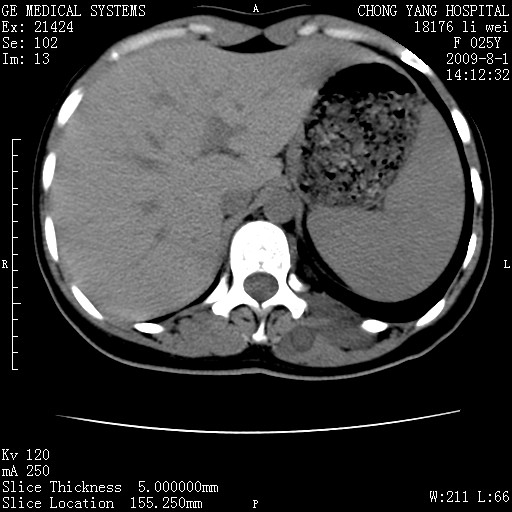

以下是引用pujunzhi在2009-8-1 20:23:00的发言:[br]胸椎旁及背部肌间良性病变,范围广,边界清,沿肌间生长,考虑淋巴管瘤、血管瘤,建议增强扫描。